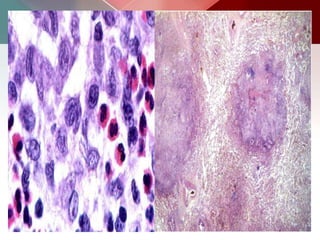

 The earliest histologic lesion of PLCH consists of proliferation of

 The characteristic lesion is composed of variable numbers of

 These granulomas are typically centered around distal bronchioles,

 As these cellular granulomas evolve, peripheral fibrosis forms

 Evolution from nodule, through cavitating nodule and thick walled

Alveoli which aredistended with honey- combed, foamy, brightly eosinophilic material . There is a scanty inflammatory infiltrate composed mainly of monocyte, occasional plasma cells and histiocytes.